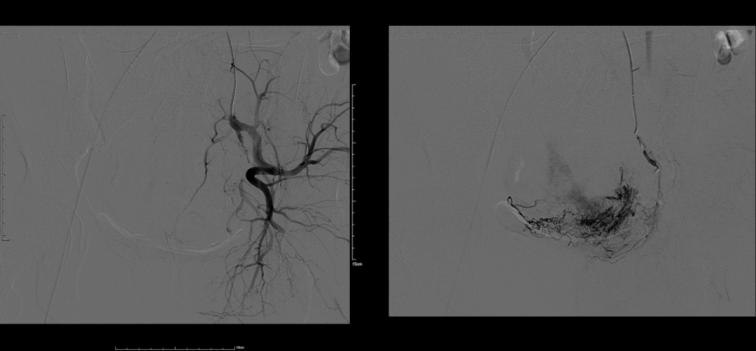

我院科教院長(zhǎng)、婦產(chǎn)科專家盧北燕、婦科主任劉小立帶領(lǐng)婦科團(tuán)隊(duì)認(rèn)真分析患者病情,入院診斷為:剖宮產(chǎn)術(shù)后子宮瘢痕妊娠。為了保留患者的生育功能,確保患者生命安全,我院婦科在患者入院第一天行子宮動(dòng)脈栓塞介入手術(shù),隔日于全麻下行宮腔鏡檢查術(shù)+宮腔鏡剖宮產(chǎn)瘢痕妊娠病灶切除術(shù)。術(shù)后病理送檢組織為妊娠絨毛、滋養(yǎng)細(xì)胞、蛻膜及凝血組織?;颊咝g(shù)后恢復(fù)良好,三天出院。

子宮動(dòng)脈栓塞與清宮術(shù)或?qū)m腔鏡手術(shù)結(jié)合,是目前臨床上較為常用的治療方式。經(jīng)股動(dòng)脈插管向子宮動(dòng)脈注入栓塞劑能迅速有效止血;栓塞后在B超或?qū)m腔鏡監(jiān)視下清除胚囊絨毛,使術(shù)中大出血的風(fēng)險(xiǎn)大大降低。目前,我院婦科已經(jīng)成功開展多例此類介入手術(shù),深得廣大女性患者的認(rèn)可。未來,佳木斯大學(xué)宏大醫(yī)院全體醫(yī)護(hù)人員將一如既往地為三江百姓健康保駕護(hù)航。